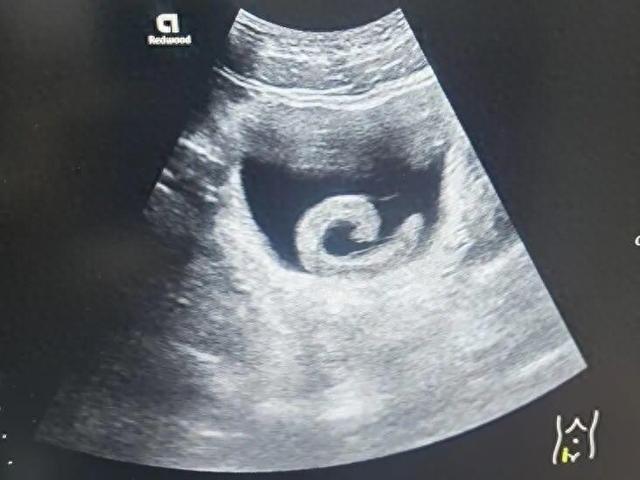

23岁男子信偏方把5cm水蛭塞进尿道!近日,河南郑州一名23岁的年轻人小郑在网上看到一些所谓的“偏方”后,出于好奇和猎奇心理,竟然网购了一条活体水蛭并将其塞入了自己的尿道。起初,他期待某种“奇特”的效果,但很快剧烈的疼痛和排尿困难让他意识到问题的严重性。水蛭顺着尿道爬到了膀胱,并开始吸血和释放抗凝血物质。小郑随即前往郑州市人民医院就诊。

泌尿外科副主任医师马曜辉为小郑进行了经尿道膀胱异物取出术,手术顺利,解除了尿道梗阻,小郑的疼痛也瞬间消失。事后,小郑对自己的行为感到后怕和悔恨。

泌尿外科主任单中杰指出,这类将异物塞入尿道的患者每年都会接诊数例。这种行为不仅有手术风险,还可能对尿道和膀胱造成二次损伤,导致慢性疼痛、排尿功能障碍、反复感染以及尿道狭窄等长期痛苦。23岁男子信偏方把5cm水蛭塞进尿道!